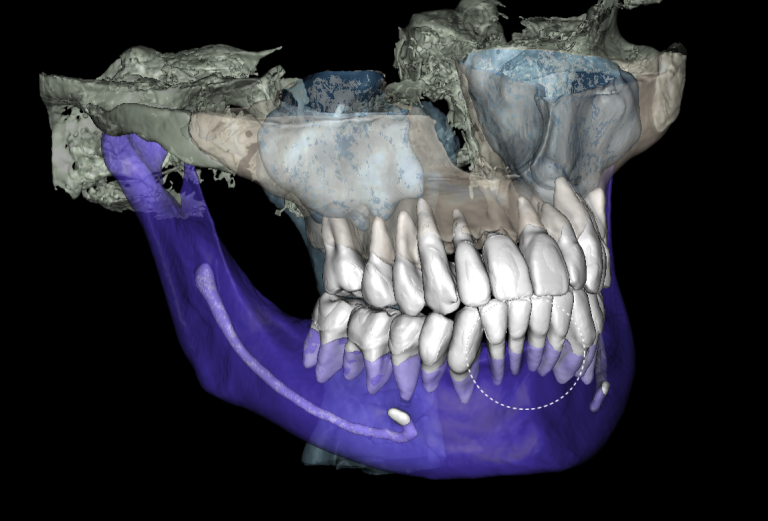

With the help of Diagnocat STL reconstruction, the doctor can visualize changes in the level of bone relative to the roots of the teeth, which are hidden behind the gum.